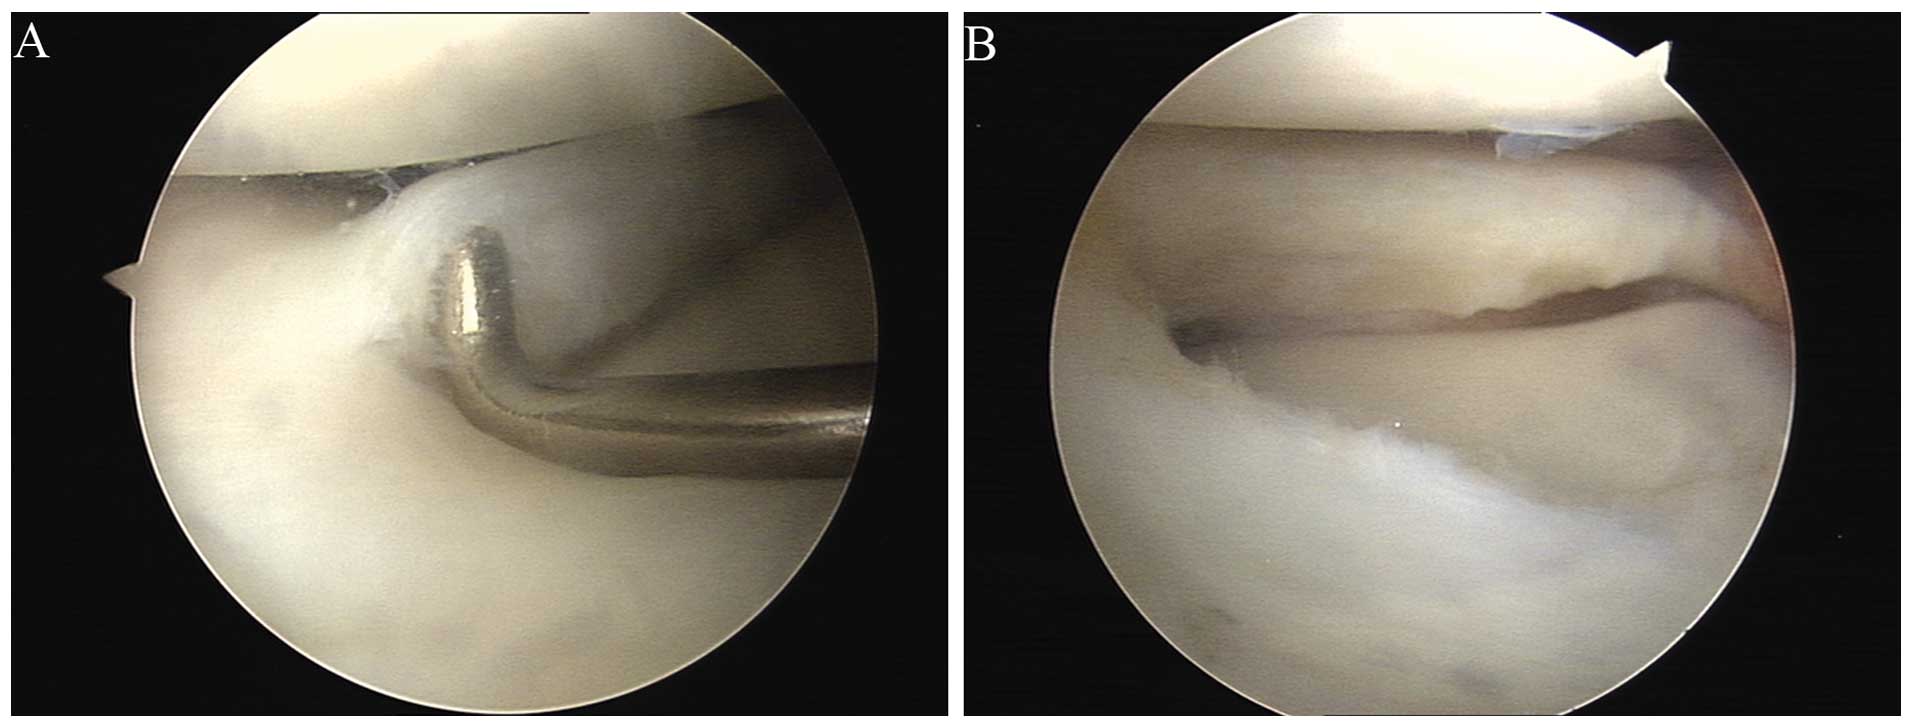

A meniscus punch (oval punch) has been introduced into the joint to perform a partial resection of the loose flaps of the torn meniscus. Knee arthroscopy, a minimally invasive procedure, is often used to treat meniscal tears. Fda registered class i & ii medical devices for home use. Recovery and rehabilitation take a few weeks. The surgery requires a few small incisions and takes about an hour. See meniscus tear stock video clips. This can happen during sports or even during normal daily activity. Details on knee surgery meniscus tear costs. What is the healing time for a meniscus tear? American technology, made in usa. Fda registered class i & ii medical devices for home use. What is the recovery time for knee repair? What are the symptoms of a torn meniscus in the knee?

Meniscal tears can also occur in the setting of arthritis. During an arthroscopy, a small, lighted, optic tube (arthroscope) is inserted through a small incision in the joint. A meniscus punch (oval punch) has been introduced into the joint to perform a partial resection of the loose flaps of the torn meniscus. Recovery and rehabilitation take a few weeks. The first choice for professional athletes worldwide.